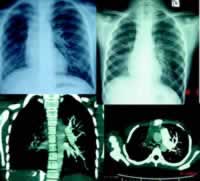

病例1 患儿,女,8岁。因间断咯血9天入院。入院前9天患儿无诱因出现轻微咳嗽,最初咳灰白色痰一次,后转为咯血,为鲜红色,不含痰液,每次约0.3~0.5 ml,在3天内咯血5次,不伴发热、胸痛及呼吸困难。当地就诊X线胸片检查示:双肺纹理增多粗糙,可见部分间质改变(见图1)。入院前2天来院查血常规示白细胞5.5×109/L,中性粒细胞49.5%,血色素126 g/L,血小板260×109/L,C反应蛋白(CRP)小于8 mg/L。门诊以“咯血待查”收入院。患儿于发病前无外伤及异物吸入史,既往体健,无特殊病史,否认结核接触史。

肺CT:右肺体积小,右肺血管略显纤细,右侧肺野渗出病变,右肺中下叶部分网格影和泡状空腔样改变,支气管壁增厚,支气管血管束部分扭曲。心脏彩超:未见异常。